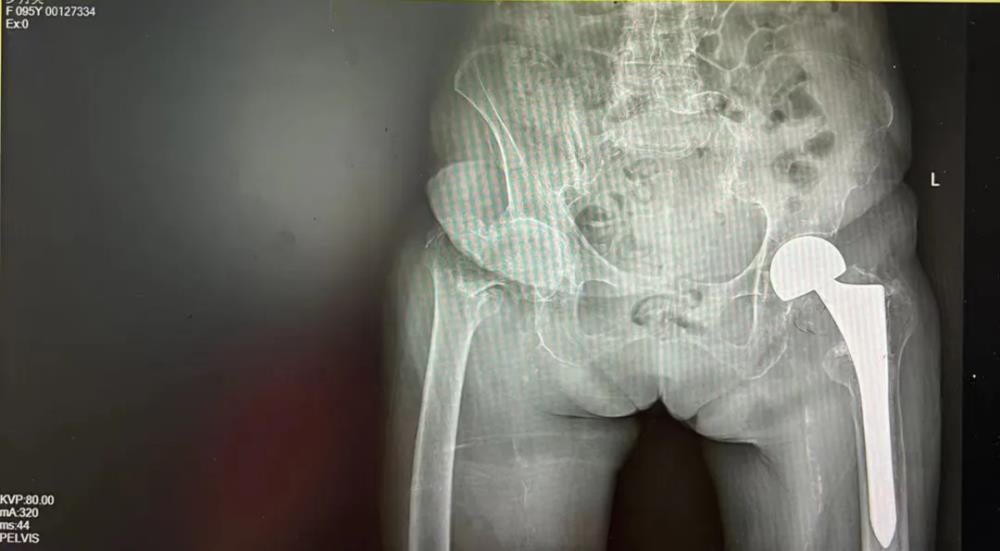

钦州市浦北县有这样一位老人,岁月在她的脸上刻下了深深的痕迹,却未能磨灭她眼中的光芒。罗奶奶,今年97岁高龄,是邻里间公认的“不老松”。然而,岁月不饶人,4年前的一次意外导致罗奶奶左股骨粗隆间骨折,在当地医院经过一次成功的髋关节置换手术后,重新站了起来。但是在今年8月初她不慎跌倒致右股骨粗隆间骨折,家属再次送到当地医院欲行手术治疗,当地医院行冠脉造影提示冠心病(三支病变,部分节段严重狭窄),认为其体质较虚弱合并严重的内科疾病,手术风险较高,不敢为其手术。随后家属带着罗奶奶住院资料到我院门诊咨询,外科与内科医生了解病情后告知家属有信心调理稳定罗奶奶的内科疾病,创造手术机会。听到医生的建议,家属急忙把罗奶奶转到我院,等待下一步的检查和治疗。

术 前

经过完善相关检查、对症治疗肺炎等内科疾病后,评估罗奶奶可耐受手术,并为其安排了择期手术。但高龄老人手术过程中可能会出现不可预料的风险和意外,面对这一挑战,罗奶奶和家人没有选择放弃,而是以一种超乎常人的勇气,决定再次接受手术。这一决定,不仅是对身体的考验,更是对意志的极大挑战。在家人和医护人员的鼓励下,她开始了有条不紊的术前准备,用乐观的心态迎接即将到来的挑战。

手术室内,我院髋关节二科团队凭借精湛的技术和丰富的经验,小心翼翼地进行着每一步操作。经过1小时的努力,手术终于圆满成功。当罗奶奶被推出手术室,那一刻,亲人攥紧的心都松了下来,掌声与泪水交织在一起,为罗奶奶的勇气和医生的精湛技术喝彩。